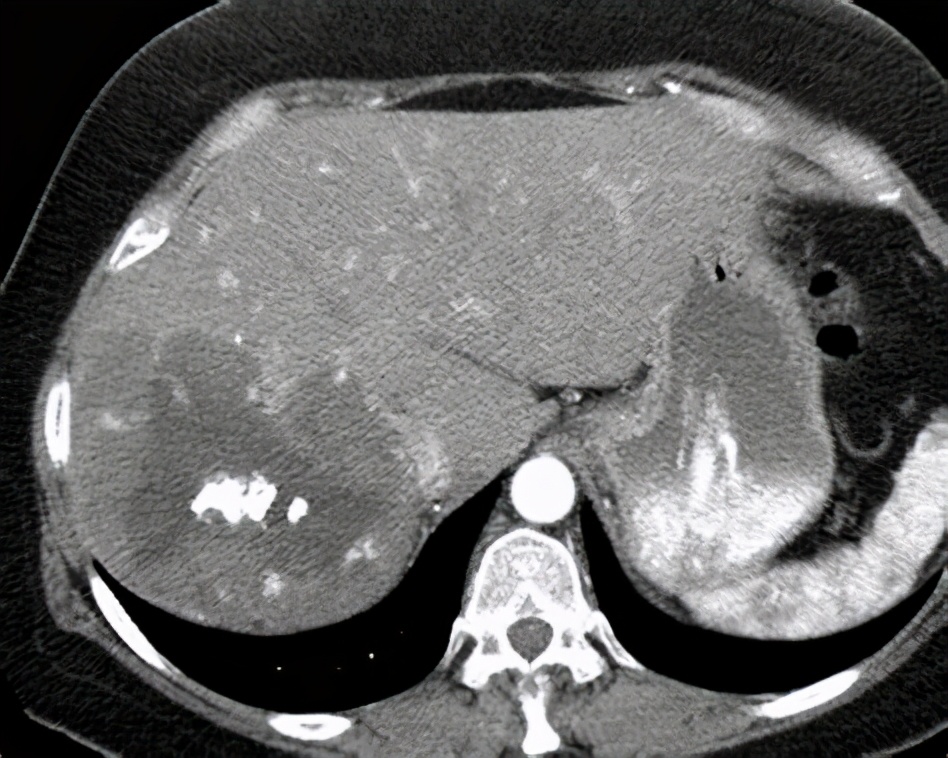

CT

要看清楚我们,CT检查是更清楚的。在CT下的我们,也是边界清楚的,呈低密度的肿块。大约10%的我们,可以同时发现里面有一些钙化灶。